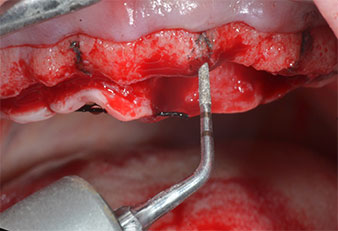

Pose d'implants

Fig. 2 : Une fois l'incision pratiquée à mi-hauteur de crête et le lambeau muco-périosté préparé, les positions implantaires sont transférées sur l’os.